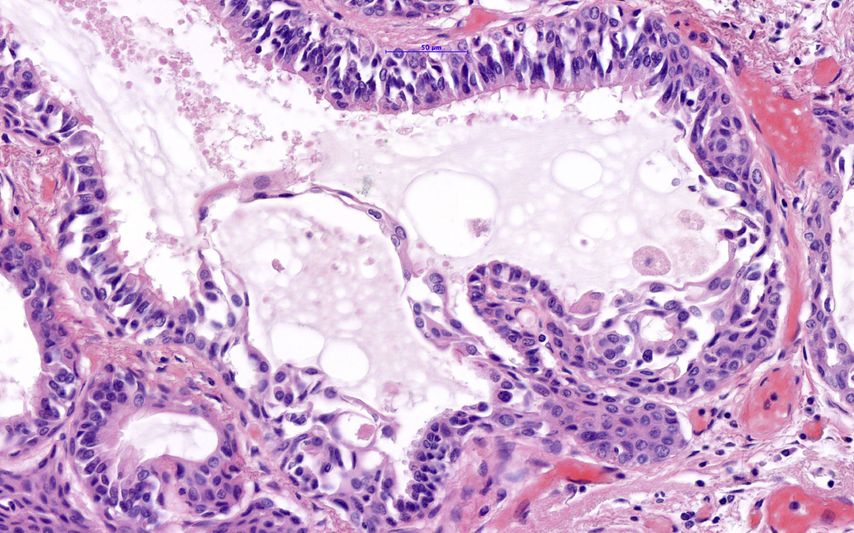

Histologisch zeigt der Tumor einen Mix aus verschiedenen Zellen: Es finden sich hochzylindrische Zellen mit Zilienbesatz (wie die normalen Zylinderepithelien), plattenepithelial differenzierte Zellen (wie eine Metaplasie mit/ohne Atypien), schleimproduzierende Becherzellen sowie Basalzellen. Die Tumorzellen exprimieren Keratin 5 (vorwiegend Basalzellen) und 7 (alle übrigen Zellen), sind teilweise positiv für den thyroidalen Transkriptionsfaktor 1 (TTF1), aber negativ für CDX2 – zeigen also keine intestinale Differenzierung. Auch eine Untersuchung auf den „hepatocyte nuclear factor 4 alpha“ (HNF4A) war negativ. Für die Becherzellen wurde eine positive Reaktion auf Mucin 5AC (MUC5AC) und MUC6 berichtet. Der Proliferationsindex Ki-67 war mit <5% sehr niedrig.

Abb. 2:Das Detailbild zeigt im Zentrum eine drüsenartige Struktur mit zilientragenden Zellen, daneben auch reichlich Schleim. Maßstab 50µm

Abb. 4:Mischung verschiedener Zellen als Charakteristikum dieses Tumors: Zilienzellen, Becherzellen, Basalzellen, Plattenepithelzellen. Maßstab 50µm

Der ziliäre papilläre mukonoduläre Tumor der Lunge ist eine neue Entität, der eine charakteristische Morphologie aufweist (Abb. 1–4). Aufgrund der bisherigen Berichte kann von einer geringen Malignität ausgegangen werden. Die molekularen Signaturen lassen aber die Möglichkeit einer Rezidivierung und eventuell sogar einer Metastasierung offen.Dementsprechend kann eine Prognose nicht mit Sicherheit abgegeben werden. Eine engmaschige Kontrolle in den ersten fünf Jahre nach Diagnose ist zu empfehlen.